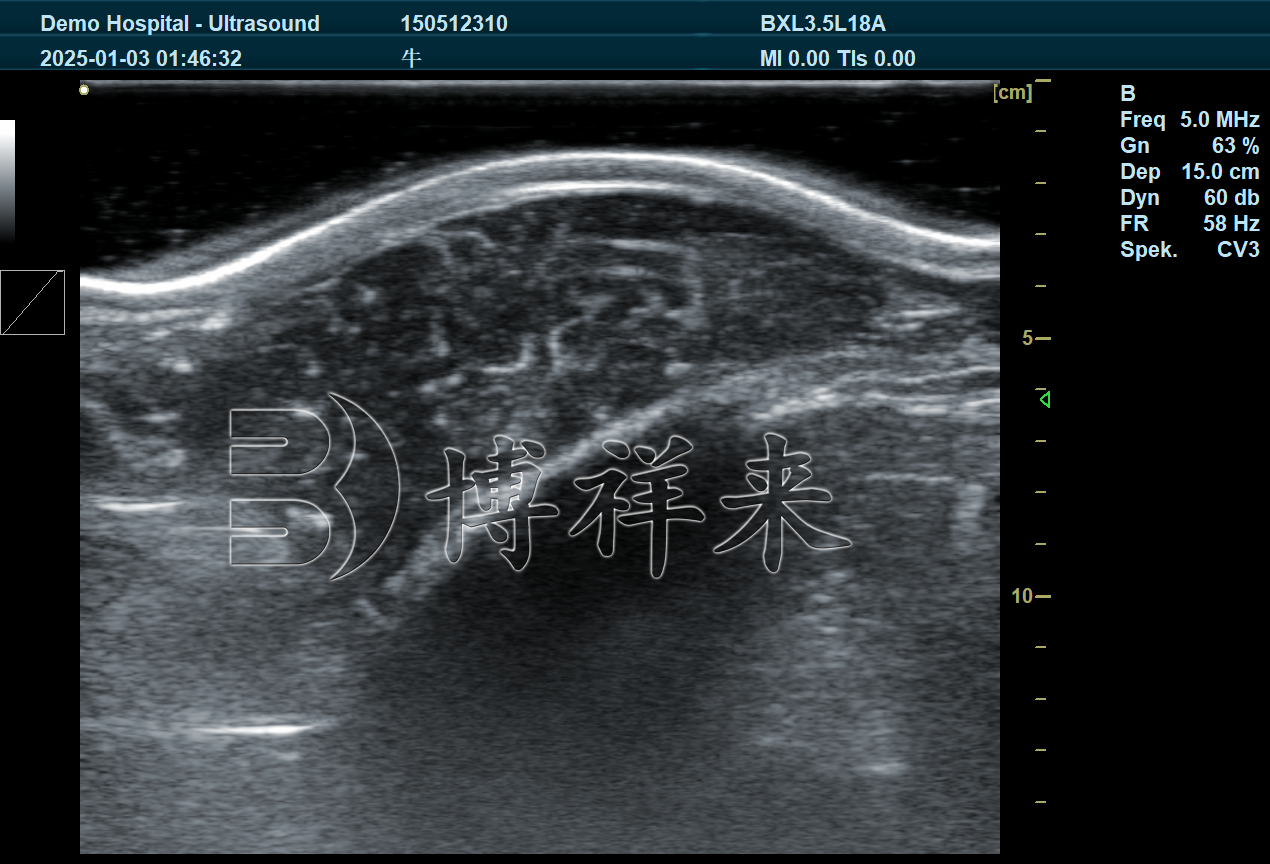

背膘仪其实就是一种肉牛育种用B超机,它通过超声波技术,无创测量牛只背部脂肪层厚度(即背膘厚度)和眼肌面积。这些指标是判断肉牛体型发育、肉质潜力和出肉率的重要参考,对肉牛选种育种具有很高的应用价值。

背膘厚度可以反映牛只的脂肪沉积情况,脂肪适中说明牛只营养均衡,有利于形成理想的肉质口感。而眼肌面积则是衡量瘦肉量的一个重要参数,眼肌越大,代表牛只的瘦肉率越高。

通过使用B超设备检测这两个指标,养殖户不再需要宰杀牛只就能直观了解其肉质潜力,大大提高了育种效率和决策的科学性。